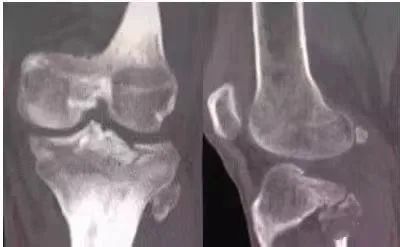

(6)胫骨髁骨折

股骨髁部骨折:暴力强大,压痛点在股骨髁部,X线片示股骨髁骨折。